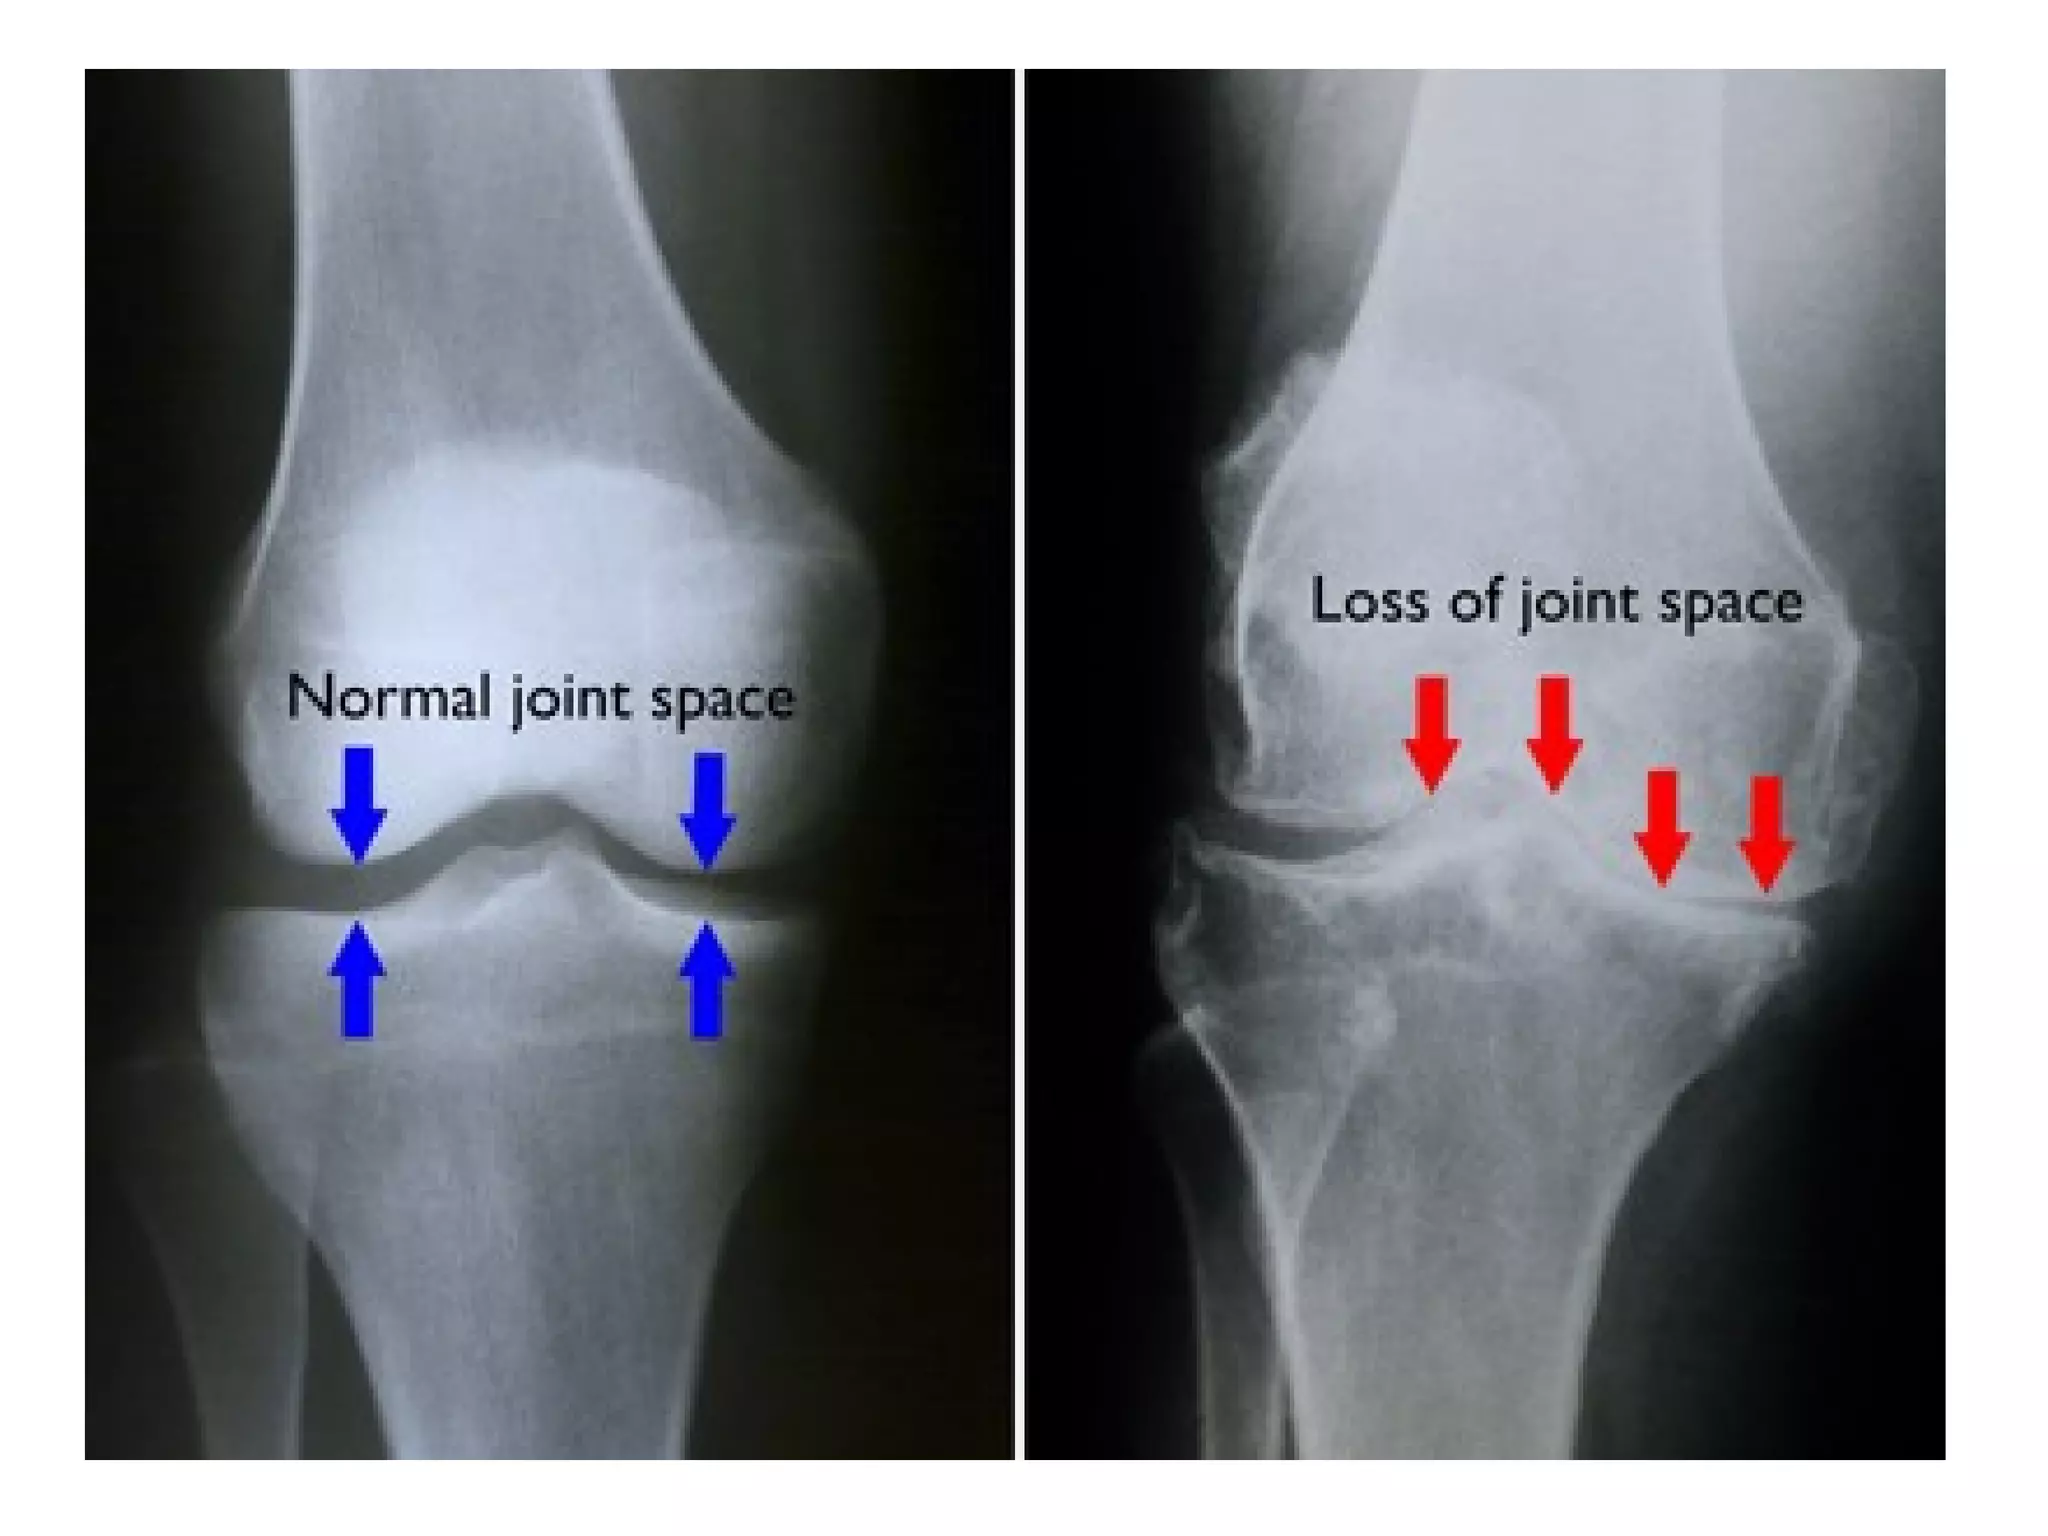

c) Radiographic Features : 5 hallmarks

1-Narrowing of joint space , usually

asymmetrical

In the knees , primary OA predominately involves the medial tibiofemoral and

patellofemoral compartments , the asymmetric medial joint space loss (white

arrow) causes a varus deformity on standing radiographs , a large

osteophyte classically forms on the medial tibial articular margin (red

arrow) , subchondral sclerosis and cyst formation may also be found

4-RA in knee :

-Joint effusion

-Typically involves the lateral or non-weight

bearing portion of the joint

-Loss of joint space involving all three

compartments (medial & lateral tibiofemoral and

patellofemoral) , in contrast , OA tends to first

affect the medial tibiofemoral articulation

-Lack of subchondral sclerosis and osteophytes

(cf OA) , if osteophytes & symmetrical cartilage

space narrowing are present then secondary OA

should be considered

Uniform joint space loss (yellow arrows) , unlike the medial compartment preference of osteoarthritis

(OA) , erosions may occur but they are not as prominent as in the hands , there are no